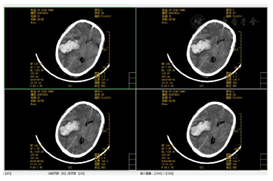

2019年8月3日急诊头颅CT提示:右侧脑出血,伴蛛血(图1)。2019年11月27胸日部CT提示:肺部感染,部分实变(图2、图3)。呼吸功能评估:胸廓活动度明显下降,呼吸肌肌力和耐力下降,无自主咳嗽。绿染实验提示患者有误吸,无食道反流情况。吞咽功能评估:存在误吸,咳嗽力量欠佳,口腔运送能力差,吞咽启动明显延迟,咽缩肌无力,下颌运动受限。

脑出血恢复期定位:右侧基底节区、右侧颞顶叶。定性:出血性脑卒中。诊断依据:入院完善颅脑CT明确诊断。